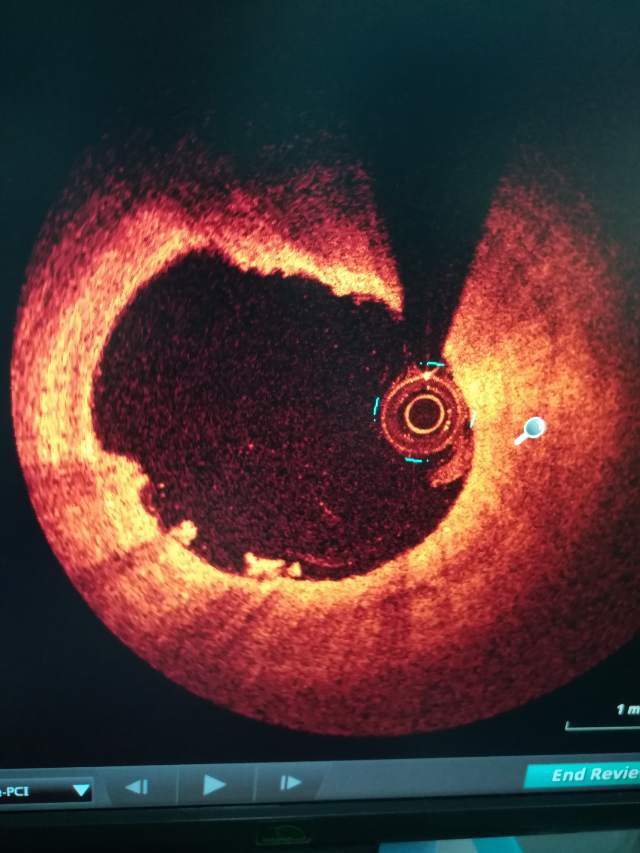

七。心脏磁共振 常用于判断心肌病,心肌是否缺血和评估心功能。但检查时间长,使用相对比较少。一般医院都不开展。                                              八。血管内超声 (IVUS) 和光学相干检查(OCT) 这两个对于了解血管内结构特别有意义,主要用于心脏冠状动脉狭窄和斑块情况的精细评估。对心脏支架植入前后的评估也有非常重要的意义。